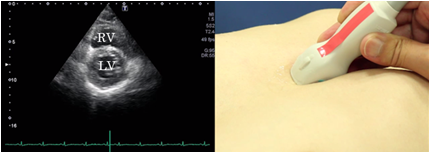

Epigastric short axis view

To obtain the epigastric short axis view, rotate the probe from the position of the epigastric 4 chamber view 90 degrees counterclockwise. The view at the epigastric site is effective when depiction of the parasternal approach is difficult due to such diseases as pulmonary emphysema.